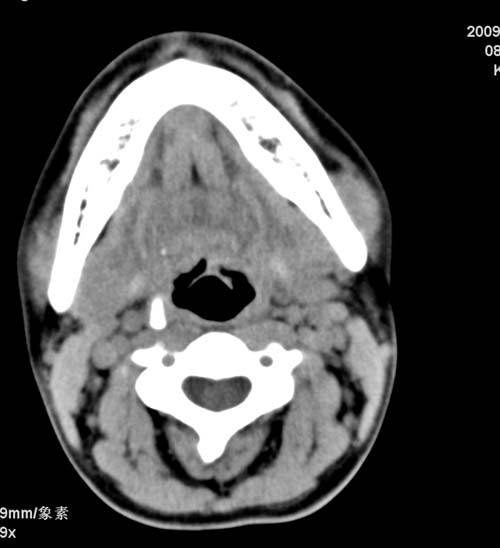

标题: CT22662:女 23 自述双侧颌下腺肿大年余 近来疼痛 左侧明显 [打印本页]

标题: CT22662:女 23 自述双侧颌下腺肿大年余 近来疼痛 左侧明显

见双侧颌下腺略肿大  未见结石及钙化 考虑双侧慢性炎症 ?请指教